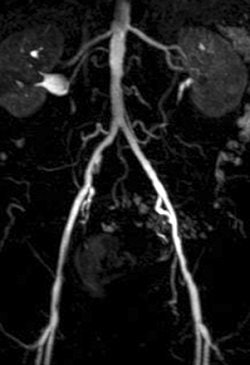

Of the nine patients, the majority had arterial occlusive disease of the iliac axis. The patients underwent angiography and angioplasty with a 6-French introducer left in the common femoral artery.

For the patients, maximum intensity projections (MIPs) were calculated from the contrast-enhanced images. Image quality for evaluating the renal arteries was graded on four-point scale (1 = excellent, 4 = poor). In the phantom, intraluminal signal intensity was measured distal to the tip of the catheter along the tube.

| A 78-year-old man with peripheral arterial occlusive disease. Lumbar arteries are evident with both MRI acquisition techniques. Iliac axis has good runoff on both sides after percutaneous transluminal angioplasty (above). Anteroposterior maximum intensity projection 3D fast low-angle shot (FLASH) intra-arterial MR aortogram obtained with standard technique (below). |

According to the results of the patient study, both techniques were well tolerated and had no side effects. In addition, the diagnostic value of GRAPPA MRA was given an average grade of 2.2 compared to 2.0 for FLASH MRA. Using the parallel acquisition technique, the CNR ranged from 32.0 in the renal arteries to 125.5 in the aorta.

In the phantom, the mean CNR ranged from 290-717 with GRAPPA MRA and 230-585 with FLASH MRA. A 15% to 26% increase in CNR was calculated for the GRAPPA MRA scans.